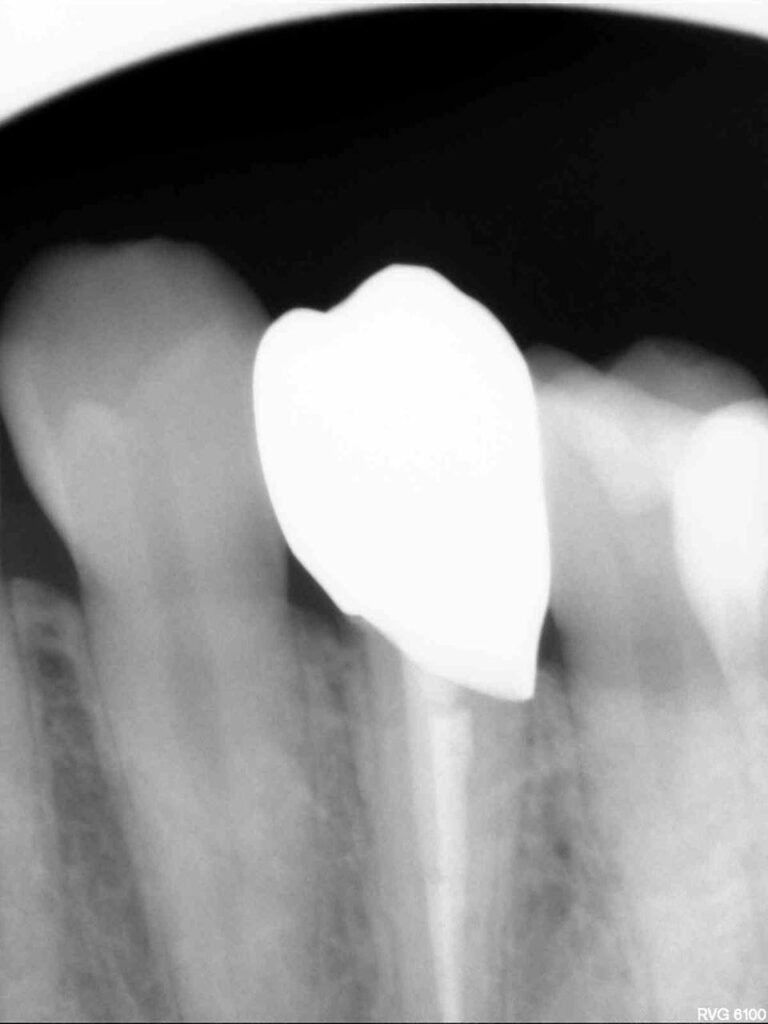

Специализация: терапия(эндодонтия), ортопедия, имплантология.